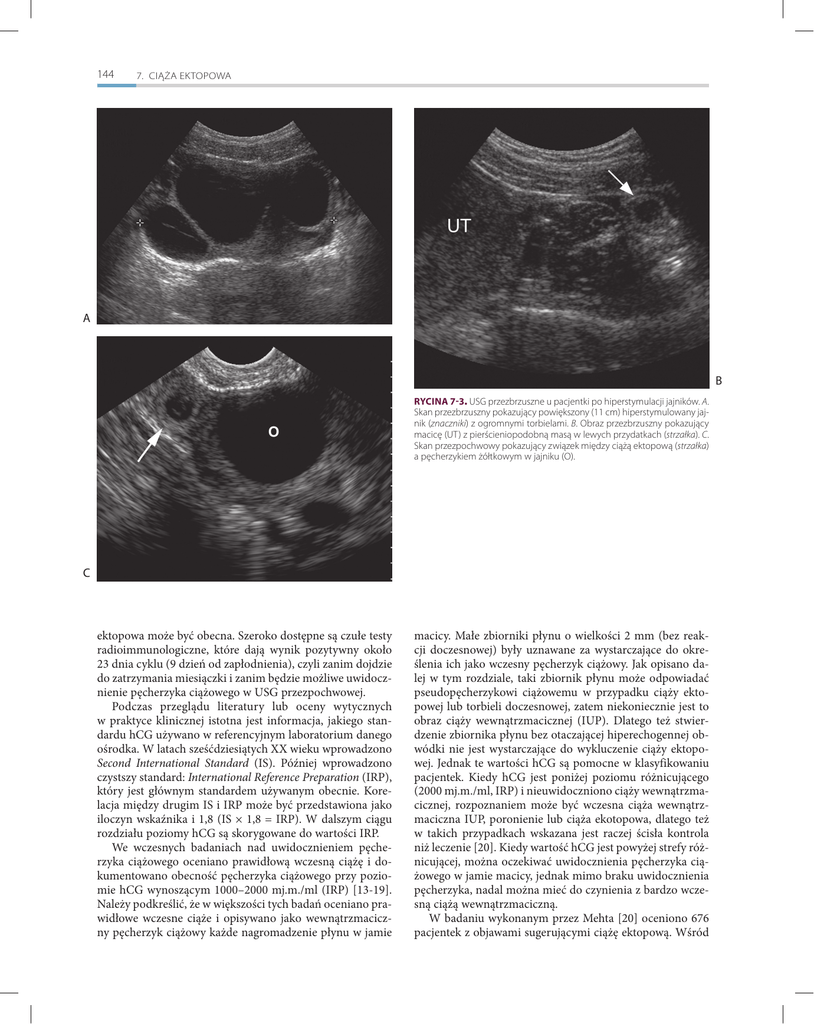

RYCINA 7-3. USG przezbrzuszne u pacjentki po hiperstymulacji jajników. A.

macicę (UT) z pierścieniopodobną masą w lewych przydatkach (strzałka). C.

Skan przezpochwowy pokazujący związek między ciążą ektopową (strzałka)

a pęcherzykiem żółtkowym w jajniku (O).